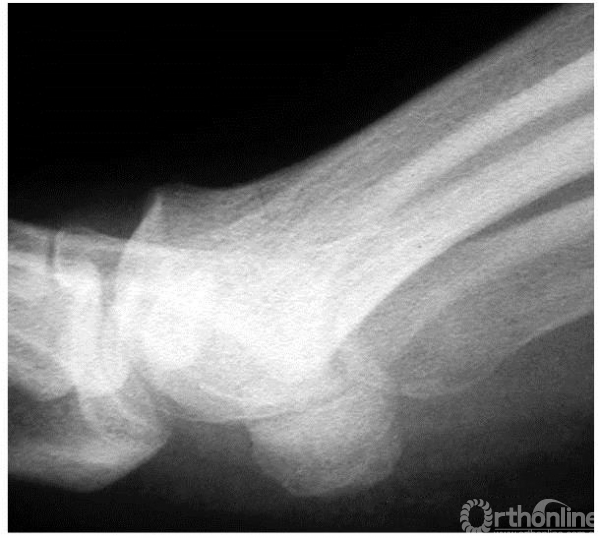

1期:侧位x线上,箭头示小的背侧骨赘

2期:侧位X线上,关节间隙变窄,但累及小于1/4的关节间隙(主要累及背侧关节间隙),背侧骨赘较为明显

3期:侧位X线上,关节间隙变窄,累及超过1/4的关节间隙,背侧骨赘更为明显